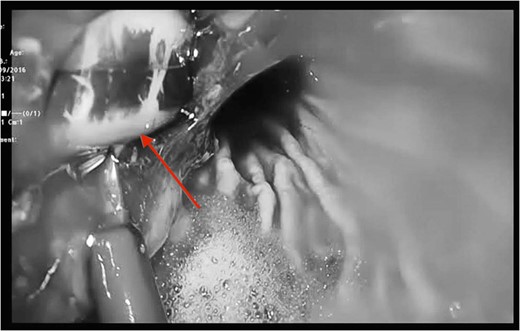

The gold standard investigative modality is endoscopy [5]. CT is another option, although such tool is more useful in detection of associated complications such as extend, site and type of perforation and/or contaminations. Upon detection of erosion, removal remains the only option and should be performed promptly to avoid associated mortality and morbidity. The use of prophylactic antibiotics in such circumstance is not clear but in our centre we highly recommend their use upon suspicion of diagnosis. In case of band migration and/or erosion, endoscopic removal has shown promising results, although such technique is not always applicable and their open retrieval has been suggested and performed. Another option is standard laparoscopic division and retrieval. Although feasible and successful, this method does not always permit a comprehensive visualization, dissection and division. In our reported case, we encountered the aforementioned factors. Therefore, the decision was made to create anterior gastrotomies (extension of the port to stomach) to facilitate full division, retrieval of the gastric band and assessment of the erosion and its repair if necessary through transgastric approach. The authors believe, such procedure is safe and feasible in circumstances when standard laparoscopic retrieval is not possible. Placement of a new gastric band is usually delayed for a period of 3 months in such cases [3, 5]. In the reported case, patient made an uneventful recovery and was discharged 3 days following the procedure.